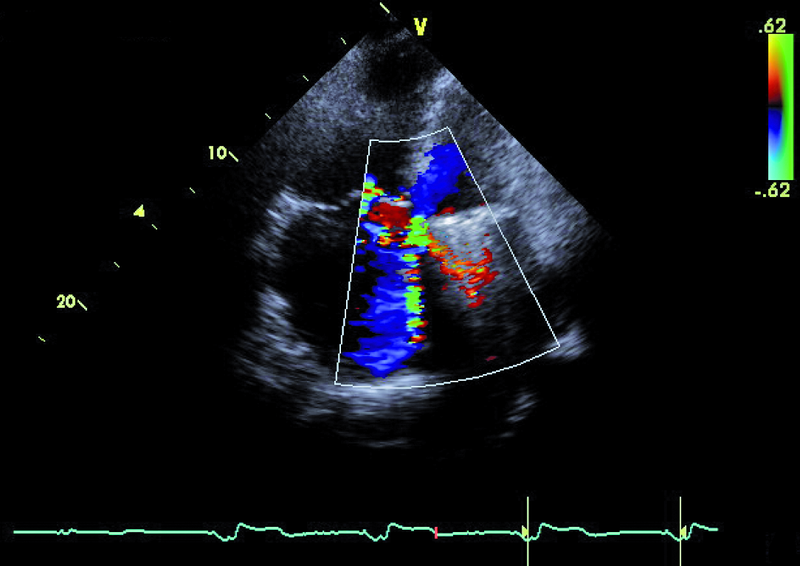

Mężczyzna, lat 59. Jakie patologie można rozpoznać na rycinach?

2. Niedomykalność zastawki mitralnej – przeciek okołozastawkowy (ryc. 2).

3. Niedomykalność zastawki trójdzielnej (ryc. 2).